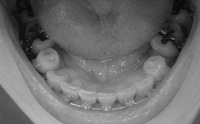

エラスティックゴムがパワーアップしました

今回のは直径4ミリ。

掛け方も前回とは逆で、下の歯を奥に引っ張ることが目的です。

左側はちょっと変則掛け。い、痛い・・・

ゴムがあんまり伸びへんから、口が開かへんー

これで限界。これ以上は痛くて無理~~~

まぁ、普通にしゃべる分にはこれでもいけるから、今回もゴム掛けがんばろう。